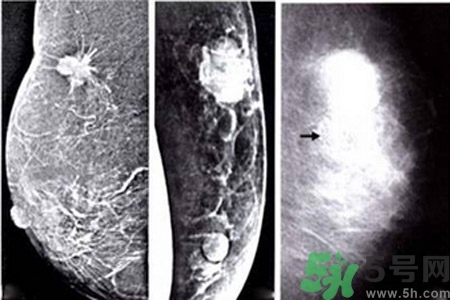

早期乳腺癌唯一的X線征象

成簇樣微小鈣化常是早期乳腺癌唯一的X線征象。根據(jù)微小鈣化形態(tài)、大小、數(shù)量和密集度等表現(xiàn)可反映病變性質(zhì)和范圍。微小鈣化點(diǎn)可位于腫塊內(nèi)或周圍,總數(shù)目6~15枚,密度不均,大小不等。

乳腺X線檢查可提高隱匿癌、微小癌(直徑小于10mm)和早期癌的診斷率。直徑小于10mm腫塊定性困難,但細(xì)沙型鈣化常是惡性病變的警報(bào);若同時(shí)出現(xiàn)周圍結(jié)構(gòu)紊亂,雙側(cè)不對(duì)稱,血管影增粗等征象則惡性病變可能性更大。

與良性乳腺增生鈣化相比,惡性乳腺增生鈣化群平均密度較低,密度及大小對(duì)乳腺疾病良惡性鑒別價(jià)值較大。乳腺X線片中微小鈣化分布似乎無(wú)規(guī)律可循,但病理發(fā)現(xiàn)癌腫發(fā)生于末梢導(dǎo)管時(shí),鈣化可位于大片壞死組織中或癌細(xì)胞間,亦可存在于所屬上級(jí)導(dǎo)管內(nèi)或?qū)Ч芊植嫣幓蛳噜徬倥萸粌?nèi)。